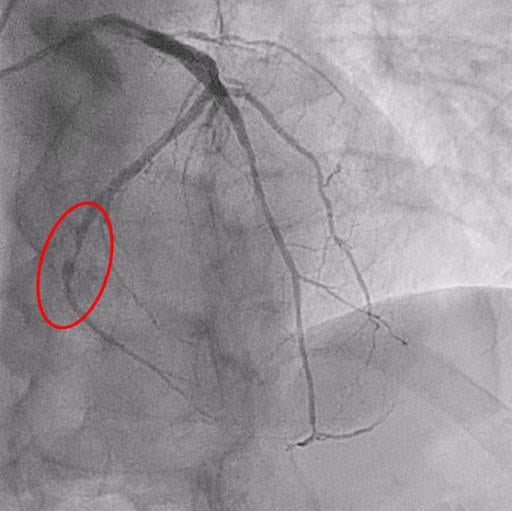

Figure 1: Critical PLCx stenosis

In the first phase, pre-dilatation is performed using semi-compliant or non-compliant balloons (vessel/device diameter ratio = 0.8-1) at nominal pressure.

A semi-compliant balloon 2.5 x 15 mm and a non-compliant balloon 3.0 x 15 were inflated up to 10 ATM and 12 ATM, respectively, to prepare the vessel.